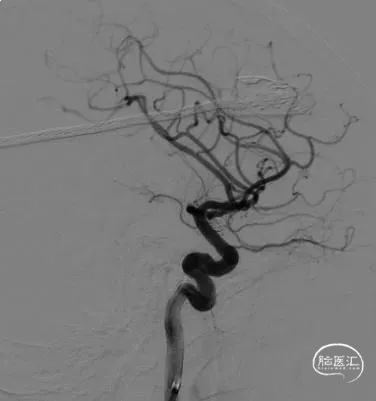

术后即刻影像

术者体会

Experience

本例为分叶状且宽颈前交通动脉动脉瘤,带子囊,需致密栓塞。成篮后用Jasper®弹簧圈继续做后续填充。Jasper®弹簧圈同时栓塞分叶带子囊动脉瘤过程中表现良好,可以很好钻空进入子囊,对子囊进行安全栓塞。选用编织支架,在支架半释放过程中,反复调整弹簧圈时Jasper®弹簧圈抗解旋能力及填塞过程中均表现优异。